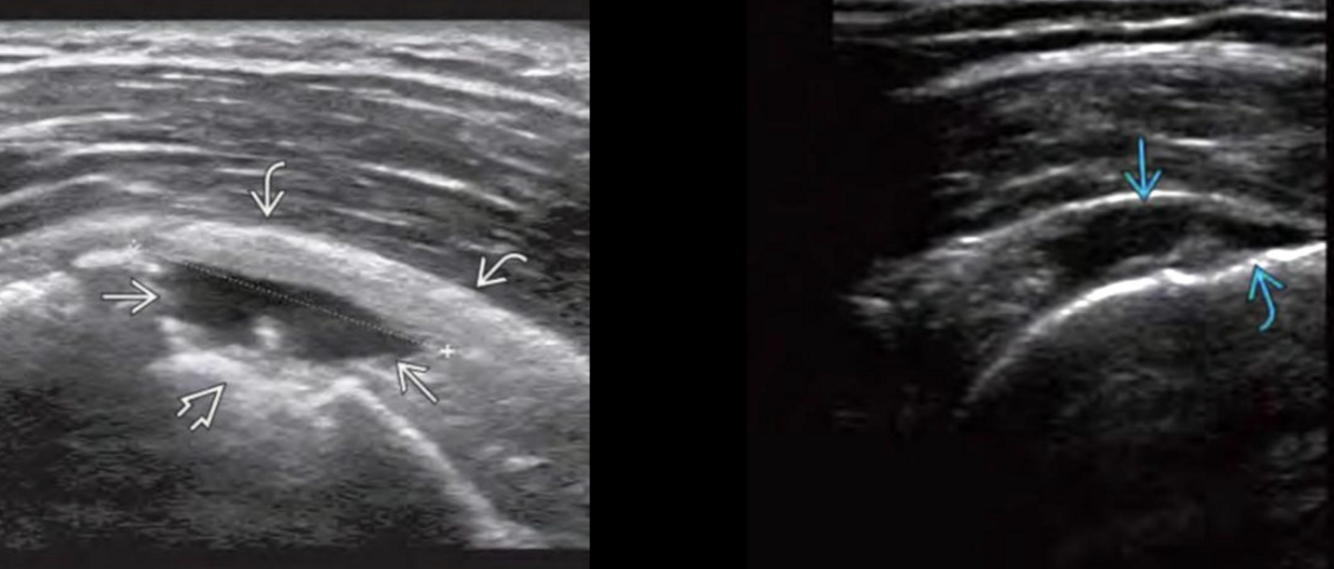

Datos de desgarro muscular en US

A

Edema y liquido

Disrupción fibrilar

Q

Desgarro muscular

Grado 1 pluma de ave

Disrupción de fibras